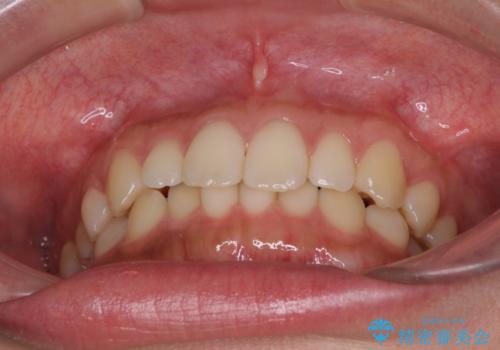

- 前歯のデコボコを気にして来院された患者様です。

治療期間中に海外勤務になる可能性が高いことが分かっていましたが、矯正治療を始めたいとのことでしたので、インビザラインを用いて治療することとしました。

通常であれば半年から10ヶ月程度で終了する歯並びでしたが、海外に長期出張することになったため、1年10ヶ月の期間を要しました。

出張に行かれてしまうと追加のマウスピースを発注できないため、マウスピースの交換頻度を低くし、一時帰国のタイミングに合わせていくことで、スムーズに進めて行くことができました。